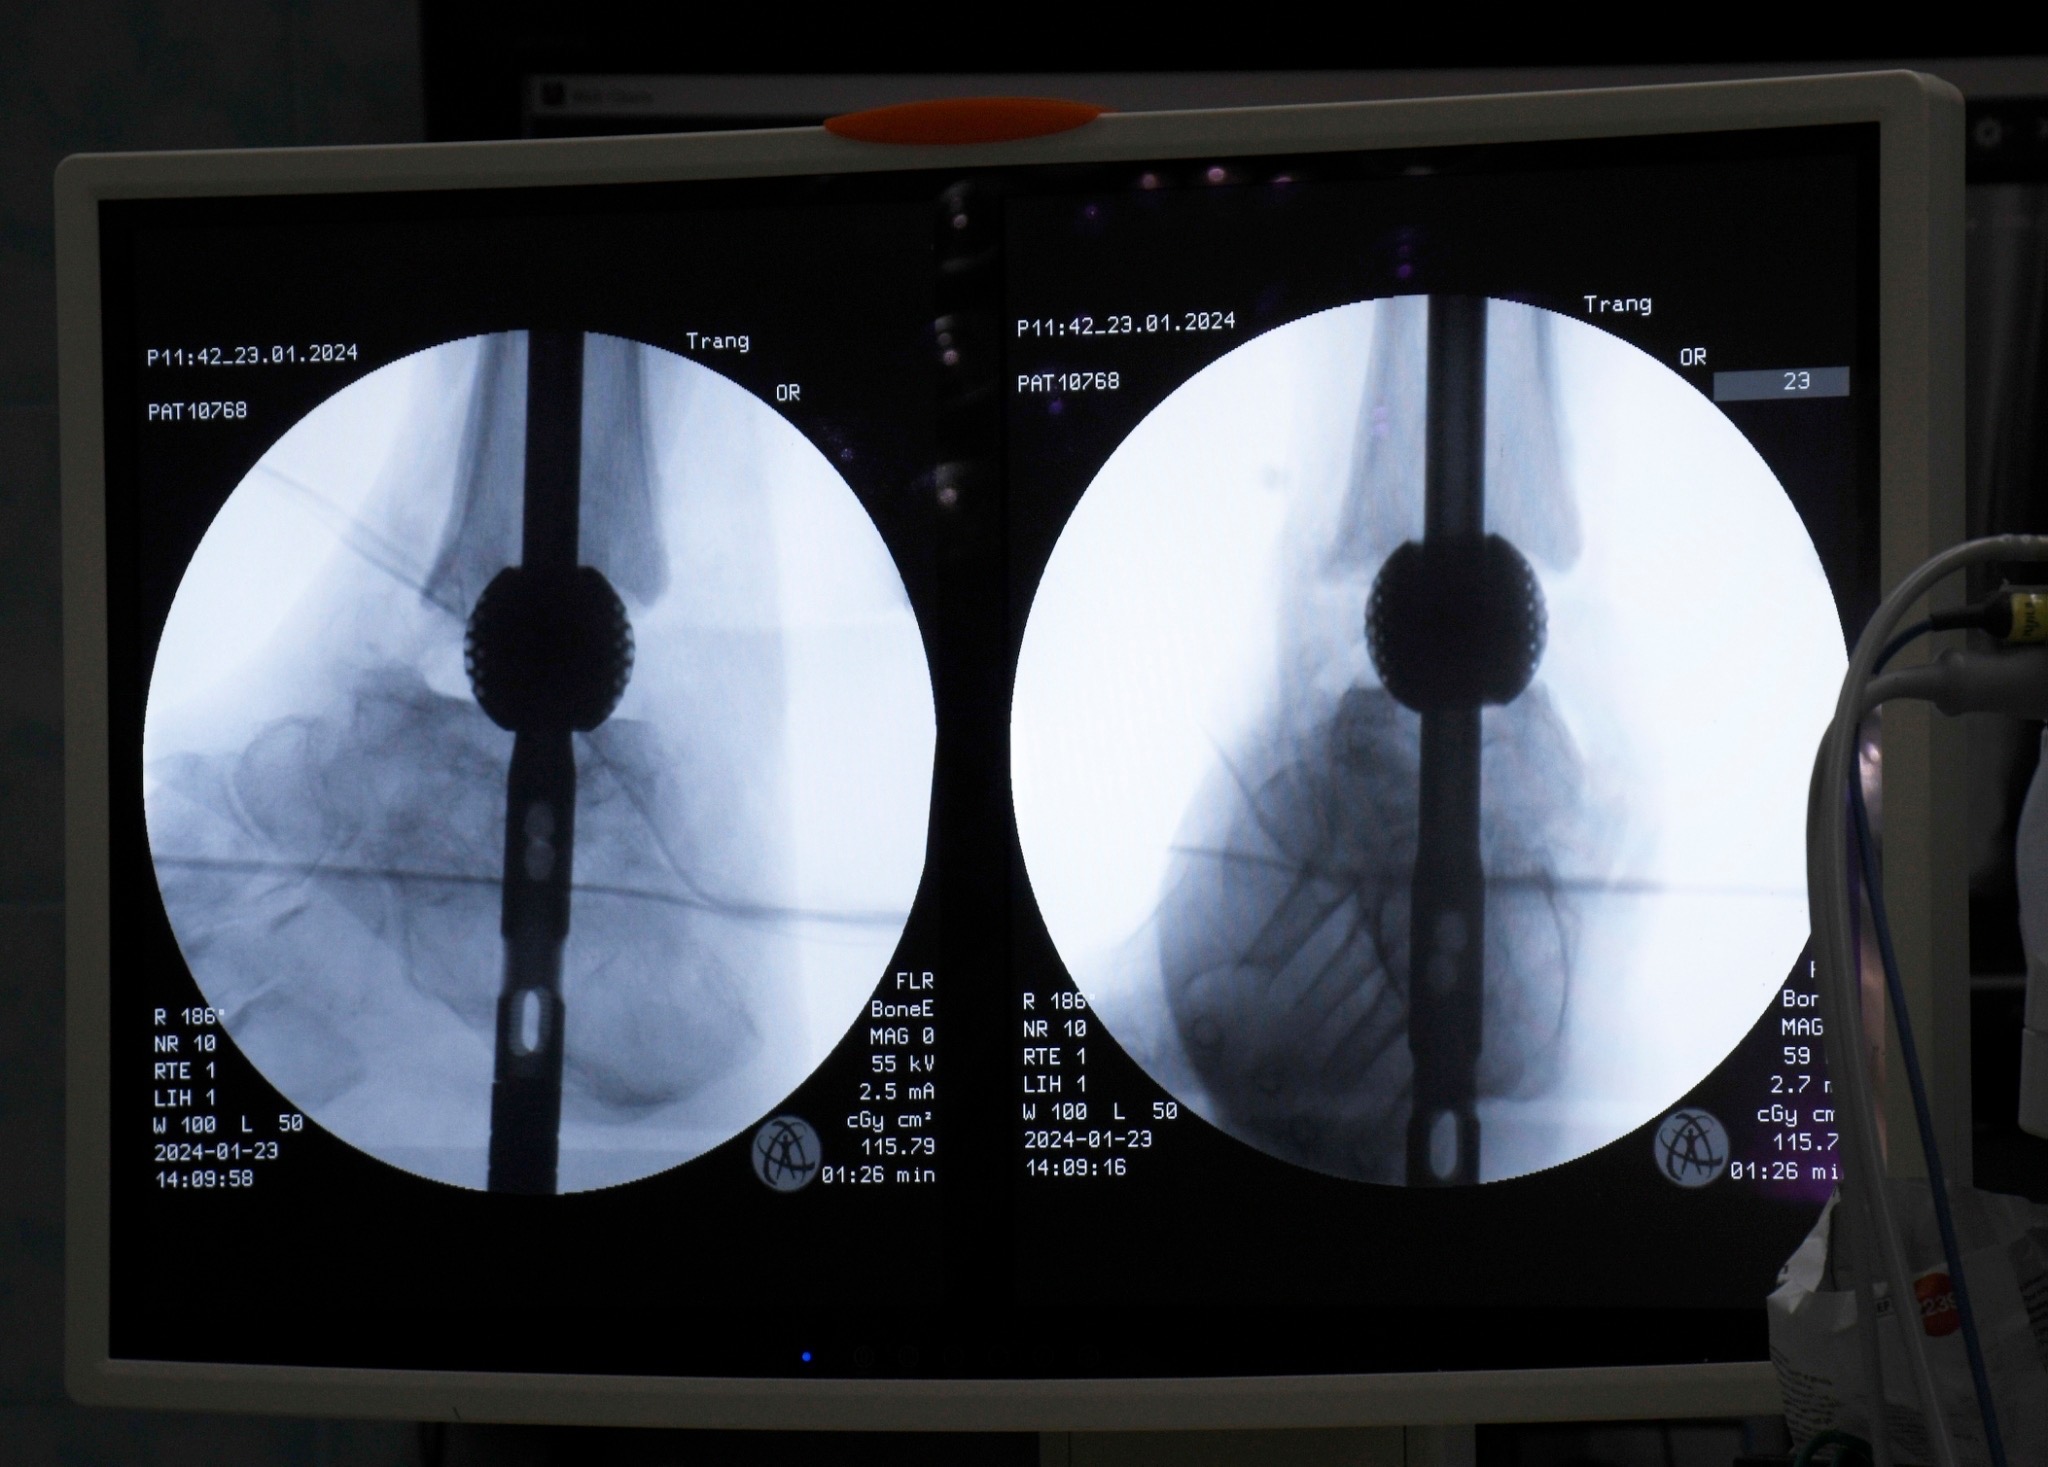

รศ.ดร.พชรพิชญ์ กล่าวว่า เทคโนโลยีนี้โดดเด่นด้วยการออกแบบเฉพาะบุคคล ความสามารถในการผสานร่วมกับกระดูกตามธรรมชาติได้ดี และลดความเสี่ยงของการติดเชื้อซ้ำได้อย่างมีนัยสำคัญ ซึ่งนำไปสู่คุณภาพชีวิตที่ดีขึ้นของผู้ป่วย ผลงานวิจัยนี้สะท้อนให้เห็นถึงความสำเร็จทางการแพทย์ในเคสที่มีความท้าทายสูง อาทิ ผู้ป่วยข้อเท้าเสื่อมที่มีภาวะกระดูกติดเชื้อจากโรงพยาบาลตรัง และผู้ป่วยกระดูกหักที่กระดูกไม่ติดกันจากอุบัติเหตุในโรงพยาบาลสงขลานครินทร์ ซึ่งทั้งหมดประสบความสำเร็จในการรักษา ผู้ป่วยสามารถกลับมาเดินได้ตามปกติ แสดงให้เห็นว่าวัสดุหรืออุปกรณ์ที่พัฒนาขึ้นนี้มีความสามารถในการปรับใช้กับกระดูกได้หลากหลายชิ้นทั่วร่างกาย ตอกย้ำถึงความอเนกประสงค์ของเทคโนโลยี

รศ.ดร.พชรพิชญ์ เล่าว่า จากแนวคิดที่เริ่มต้นเป็นเพียงงานวิจัยขั้นพื้นฐานเมื่อกว่า 2 ปีก่อน ที่ทีมวิจัยเชื่อว่าน่าจะสามารถต่อยอดไปสู่อุปกรณ์ทางการแพทย์ได้ ปัจจุบันได้พัฒนาและนำไปใช้จริงกับผู้ป่วยแล้ว ทั้งจากการติดต่อโดยตรงของผู้ป่วยและจากการส่งต่อโดยแพทย์เจ้าของไข้ ตัวอย่างเช่น กลุ่มผู้ป่วยข้อเท้าเสื่อมที่มีภาวะกระดูกติดเชื้อจากโรงพยาบาลตรัง จำนวน 7 ราย ซึ่งนำเทคโนโลยีโครงสร้างวัสดุพรุนจาก 3D Printing มาช่วยแพทย์ในการผ่าตัดรักษา

ผลลัพธ์พบว่า ภายใน 1 ปี ผู้ป่วยสามารถกลับมาเดินได้ตามปกติทุกคน จากเดิมที่ผู้ป่วยบางรายมีความเสี่ยงต้องถูกตัดขาและไม่สามารถใช้ชีวิตได้อย่างปกติ นวัตกรรมนี้ช่วยเปลี่ยนคุณภาพชีวิตของพวกเขาไปอย่างสิ้นเชิง ความสำเร็จดังกล่าวยังนำไปสู่การยื่นจดสิทธิบัตรในประเทศสหรัฐอเมริกา ร่วมกับ นายแพทย์จรวด จำปา อาจารย์แพทย์โรงพยาบาลตรัง เพื่อขยายการใช้งานอุปกรณ์สู่ระดับนานาชาติ โดยเฉพาะอย่างยิ่งกับโรคเบาหวานที่ถือเป็นปัญหาสาธารณสุขสำคัญทั่วโลก